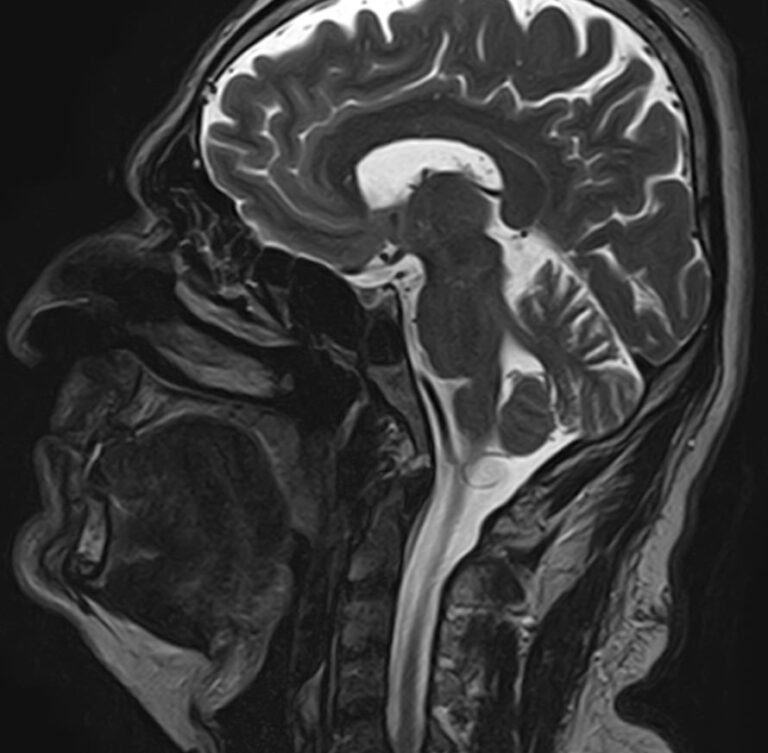

Придаточные пазухи носа представляют собой воздухоносные полости, которые располагаются в костях лицевого и мозгового черепа, выстланы изнутри слизистой оболочкой и сообщаются с полостью носа. МРТ является неинвазивным безопасным информативным способом визуализации данных анатомических областей. Метод позволяет диагностировать различные патологические процессы в области придаточных пазух носа.

Реализацию МРТ пазух носа предписывают, когда другие способы обследования больного не дают полную диагностическую картину. Это необходимо, когда нужны данные о состоянии сложно доступных клиновидных или решетчатых пазух, расположенных за костно-хрящевыми структурами черепа.

Снимки, полученные в ходе магнитно-резонансной томографии, дают подробные данные о:

Описанием изображений, полученных в ходе МРТ пазух носа, занимается врач-рентгенолог. Он же составляет заключение о подтверждении или оспаривании предварительного диагноза. Время описания может занять от 30 минут до 2 дней, в зависимости от степени загруженности клиники. Снимки передаются больному в распечатанном и электронном виде вместе с полным заключением. Результаты МРТ обязательно предоставляются лечащему врачу для определения тактики лечения, качества проведенной терапии.